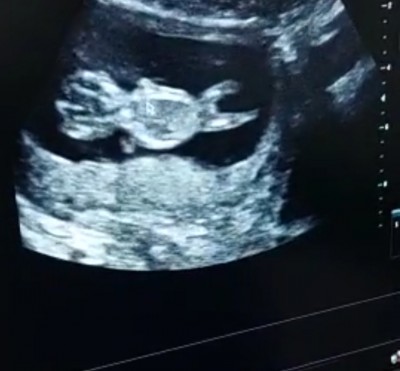

bu da diğeri canlar

Alttaki erkek gibi üsteki anlamadım cnm ama oda erkek sanırım çift yumurta ikiizimi

Ustteki erkek alttaki zaten kız  <3 saglikla gelsin bebislerin